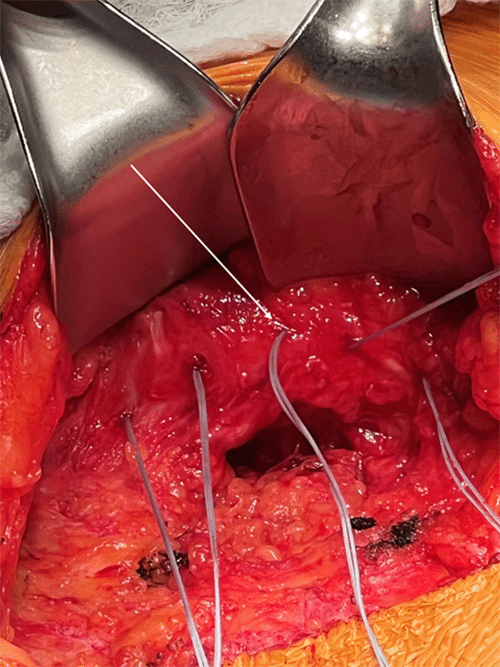

A 46-year-old woman was in a car crash nine years prior to her initial presentation. Her injuries included a complex pelvic fracture that required operative fixation on the side of the abdominal wall hernia. After discharge from rehabilitation, she noted pain associated with a bulge along the right iliac crest. A CT scan demonstrated that the right external oblique, internal oblique, and transversus abdominis muscles were avulsed along the iliac crest with colon and retroperitoneal fat herniating into the subcutaneous space. Eight years after the accident, the hernia was repaired by a surgeon from another health care system using a lightweight mesh. The mesh was positioned into the preperitoneal and retroperitoneal spaces. It was secured to the periosteum along the iliac crest with Prolene suture. Shortly after the operation, she began experiencing pain in the right side of the abdomen associated with a bulge at the area of the prior hernia. A CT scan confirmed the repair failed, and the hernia had recurred (Figure 1). The patient presented to our clinic with worsening flank and right-sided abdominal pain that limited her daily activities. Physical examination revealed a bulge along the right flank and was consistent with a recurrent hernia. She consented to proceeding with another repair of the hernia.

Figure 1. CT Scan Demonstrating Recurrent Traumatic Right Flank Hernia. Published with Permission